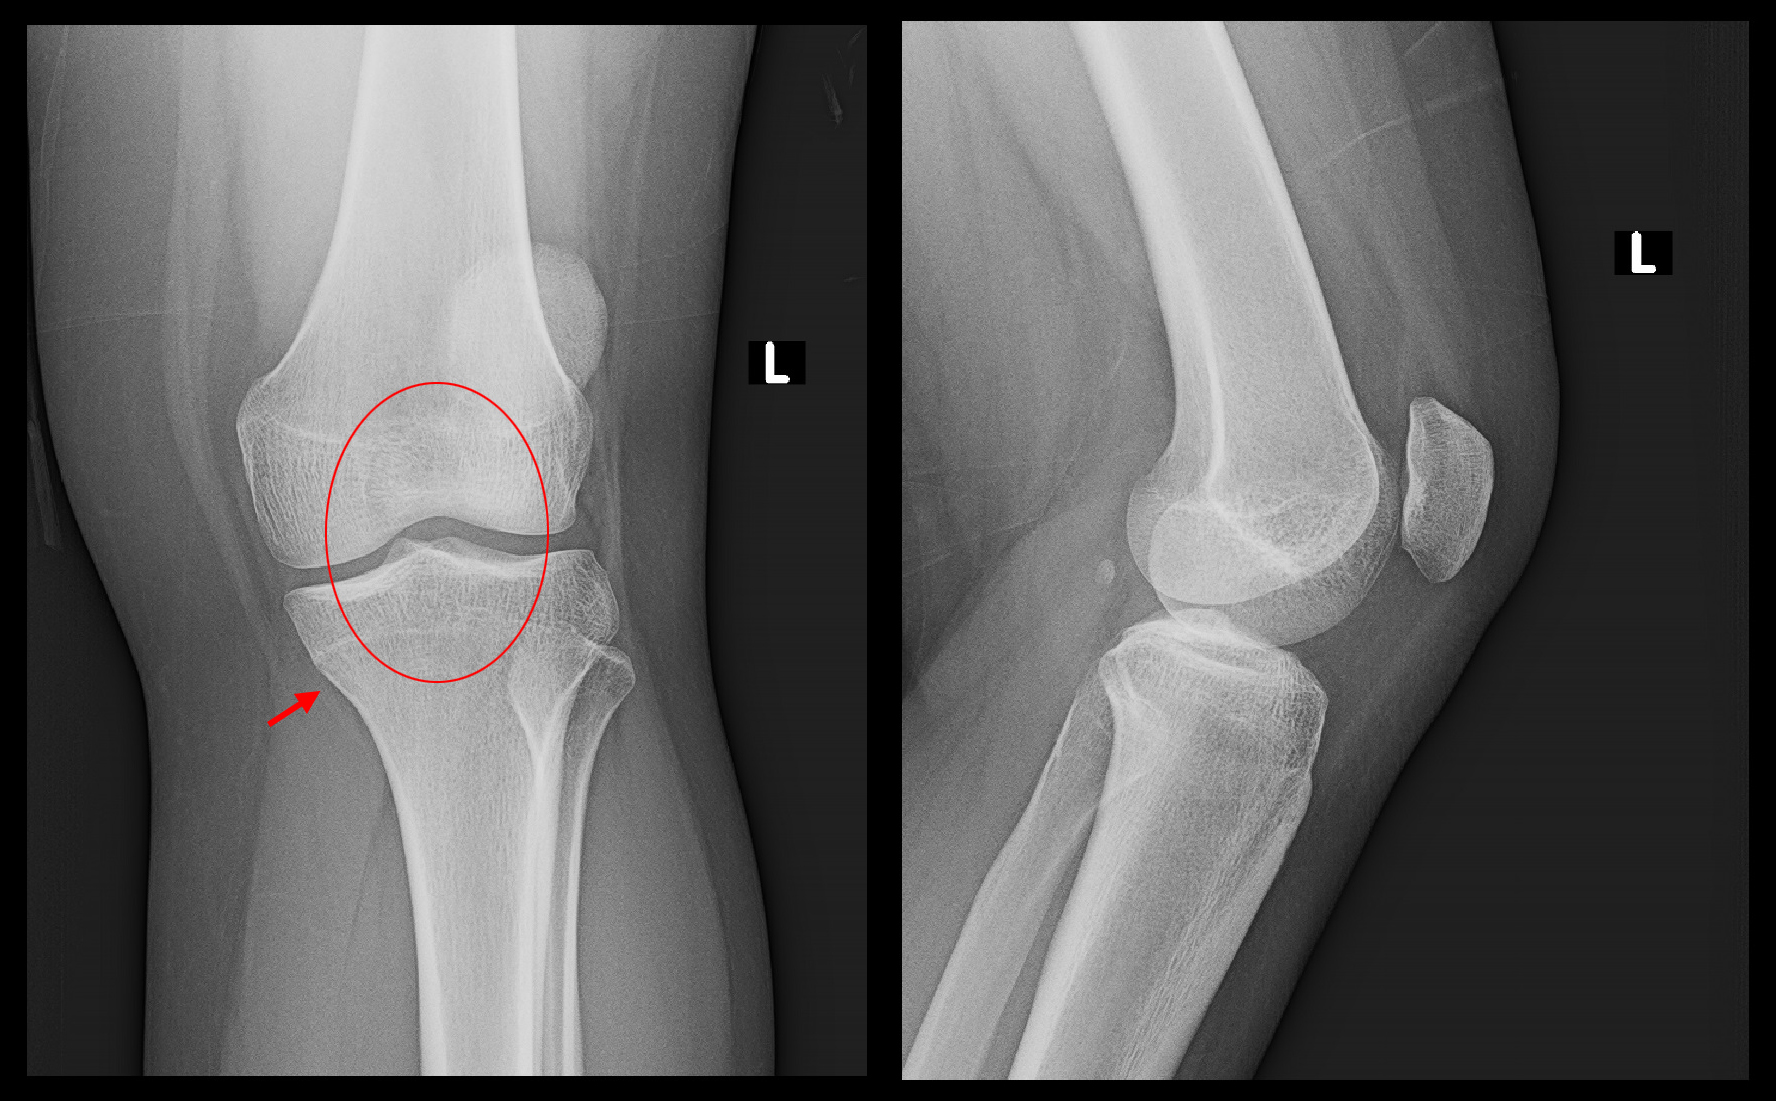

10才女 MR1.jpg

しかし、STIR冠状断という画像では右膝脛骨に疲労骨折の所見はなく、また半月板損傷の場合によくみられる内側側副靭帯の炎症所見(オレンジ矢印領域の高輝度所見)も認められませんでした。赤矢印と青矢印で内側半月板の中央先端の位置が微妙に違っています。

10才女 MR2.jpg

PD冠状断という画像では内側半月板が右では軽度の亜脱臼を示しています。

10才女 MR3.jpg

PD矢状断という画像でも、右内側半月板は軽微ですが、前方に亜脱臼していると評価できます。十分な骨格ができていないのに、過重な練習負担が加わって軽微な半月板亜脱臼が発症したと理解されます。このように若年者の膝痛でも将来変形性膝関節症に進行していく半月板亜脱臼が起こりうることをを初めて把握しました。